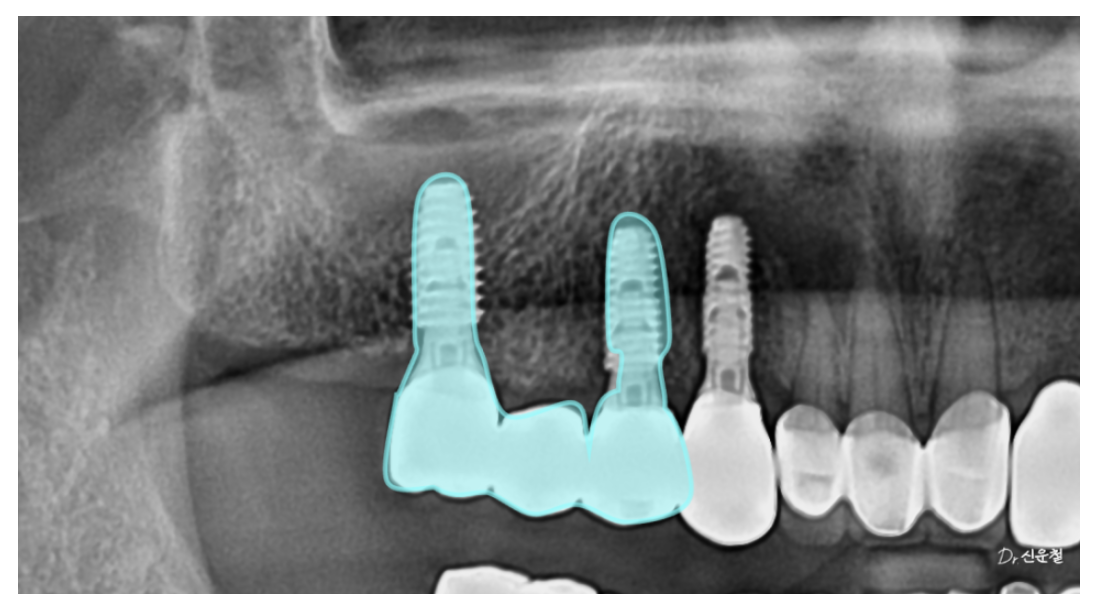

[오른쪽 치료 과정]

4개 상실 → 임플란트 3개로 복원

오른쪽은 치아가 4개 연속으로 빠져 있었습니다.

하지만 이를 한 번에 길게 연결하면

힘이 집중되어 오래 버티기 어렵습니다.

그래서

✔ 뒤쪽 힘이 안정적인 두 자리에만 임플란트를 식립

✔ 3개 치아 역할을 할 수 있도록 다리 구조로 제작

했습니다.

남은 앞쪽 1개는 단독 임플란트로 자연스럽게 회복했습니다.

그래서 우리는

임플란트 2개를 기둥으로 세우고

그 사이 치아 1개를 자연스럽게 연결하는 구조(다리 구조)를 선택했습니다.

이 방식은 수술 범위를 최소화하고

씹는 힘을 고르게 분산시키는 장점이 있습니다.